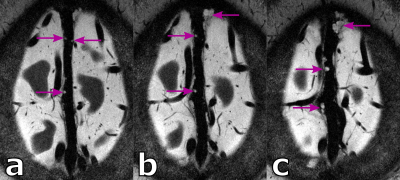

Figure 4: Arachnoid granulations (magenta arrows) shown in three consecutive axial slices of a healthy 38 years old male.